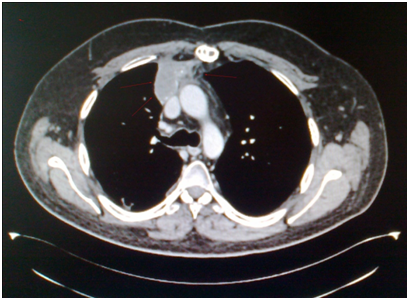

The 2nd case we report is of a 42-year-old Caucasian male who sought the gastroenterology outpatient clinic complaining of dysphagia for about 4 months. Laboratory findings were normal. X-ray with a contrast material (barium X-ray) and upper GI endoscopy were performed and the patient was treated for gastro-oesophageal reflux disease via lifestyle changes and oral medication with proton-pump inhibitors. Two months later the symptom had precipitated and after oesophageal pH monitoring was performed, surgical treatment was decided. Before the surgery, an MRI scan of the chest showed a large mass of the anterior and middle mediastinum (Bild’s 8-9). PET showed marked uptake only in the mediastinal mass. Fine needle aspirates and core biopsies yielded a poorly differentiated neoplasm. Blood tests for germ cell tumor markers showed a normal a-fetoprotein level and an elevated β-HCG level (31mIU/ml). Thoracoscopy was performed to obtain sufficient tissue and histopathological examination of a section of the neoplasia revealed a seminoma (Figure 7-12). Testicular sonography was performed to look for an occult primary tumor. The testicles were normally positioned and symmetric in size and echogenicity. No mass was present. Thoracotomy revealed a dark, solid mass adherent to the pericardium, which was removed. Patient was placed on cisplatin-based chemotherapy (BEP regimen: cisplatin 50mg/m2 on days 1-2, etoposide 165mg/m2 on days 1-3, bleomycin 30U on days 1, 8, and 15, every 3 weeks). Patient completed 4 cycles of chemotherapy without major hematologic toxicity. A subsequent chest CT revealed a decrease in the size of the middle mediastinum remaining mass (from 5,5x2,5 to 2,3x1,5cm). The fluorine-18, deoxy-2-fluoro-d-glucose positron emission tomography (PET)–computerized tomography (CT) (PET–CT) was negative for viable disease. The remaining mass was inoperable so the patient was offered follow up with 3monthly chest CT and tumour markers (b-HCG, aFP, LDH) for the first year, 4monthly for the second year and twice a year for years 4,5 and 6. Today, 76 months after the diagnosis the patient is in perfect health without any signs of relapse.

The 1st case we report is of a 22-year-old Caucasian male, who was admitted to our hospital with a 3-days history of progressive dyspnea on exertion, neck swelling, fatigue, persistent chest pain, pyrexia, and a cough that was occasionally productive of blood. The physical examination revealed a heart rate of 115 beats per minute (Sinus Rhythm), a respiratory rate of 25 breaths per minute and superficial vascular distention over the neck. Laboratory studies revealed elevated serum α-fetoprotein (AFP) (5380 IU/ml) and D-dimer (481ng/ml). A chest X-ray in the poster - anterior view, upon admission, depicted a suggestive right upper mediastinal mass (Bild 1). Radiography was followed by contrast-enhanced CT scan that revealed a large, homogeneous mediastinal mass crossing into the anterior mediastinum and compressing – encasing the superior vena cava. It also showed signs of thrombosis of the left brachiocephalic vein, and multiple filling defects at the left pulmonary artery indicating embolism. Subcarinal lymphadenopathy, as well as enlarged lymph nodes of the right hilum was present (Bild’s 2-5). On median sternotomy, a large non resectable tumor was observed involving the in nominate vein and the superior vena cava (Bild 6). Great care was taken to remove as much tumor mass as possible. To decompress the superior vena cava, we had to perform an extensive resection and reconstruction of the cephalad part of the superior vena cava using homolog pericardium.A histopathological examination of a section of the mass revealed a mixed NSGCT (embryonal yolk sac/endodermal sinus tumour), containing also elements of embryonal carcinoma (Figure 1-6).The patient was placed on cisplatin-based chemotherapy (BEP regimen: cisplatin 50mg/m2 on days 1-2, etoposide 165mg/m2 on days 1-3, bleomycin 30U on days 1, 8, and 15, every 3 weeks). Tumor markers were elevated for a-FP (214ng/mL) and normal for β-HCG. The patient completed 4 cycles of chemotherapy and the subsequent chest CT (Bild 7) revealed a partial remission of the mass (decrease>50% of the size). The a-FP was normal as well as the β-HCG. The remaining mass was inoperable so the patient was started on salvage chemotherapy with the TIP (paclitaxel, ifosfamide, ciplatin) regimen for 4 cycles. The post-chemo chest CT showed stable disease and the patient was referred to radiation oncologists for radiotherapy of the remaining tumor. Three months later af P was found elevated and the CTs revealed multiple brain metastases. Whole brain radiation was performed and the patient was placed on gemcitabine (d1 and d8 every 21 days). Two months later the neurologic status deteriorated with new brain metastases and the patient passed away (19 months after the diagnosis).